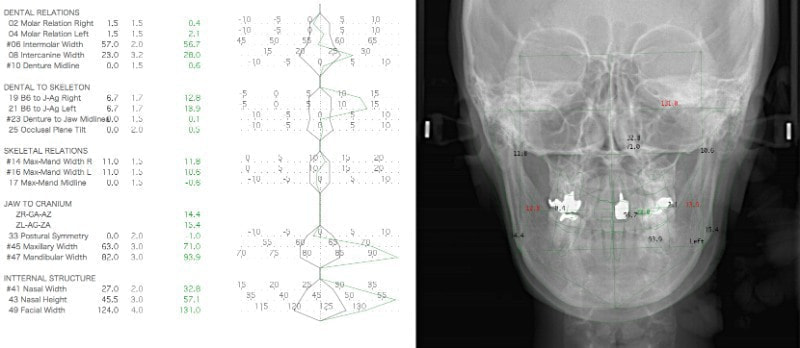

セファロ分析結果:上顎の劣成長と下顎の過成長が認められる値が出ています。重度の叢生といえます。

セファロ分析側貌

骨格的な下顎前突の傾向は強くはありませんが、歯牙の状態によって反対咬合が認められます。LowTongue(低位舌)もあります。

セファロ分析正貌

顔面の幅径はかなり狭い傾向にあります。

治療後セファロ分析側貌

舌位、気道、咽頭扁桃、口蓋扁桃、良好なEラインとプロファイルが得られております。

治療後セファロ分析正貌

顔面の対称性が確保されております。